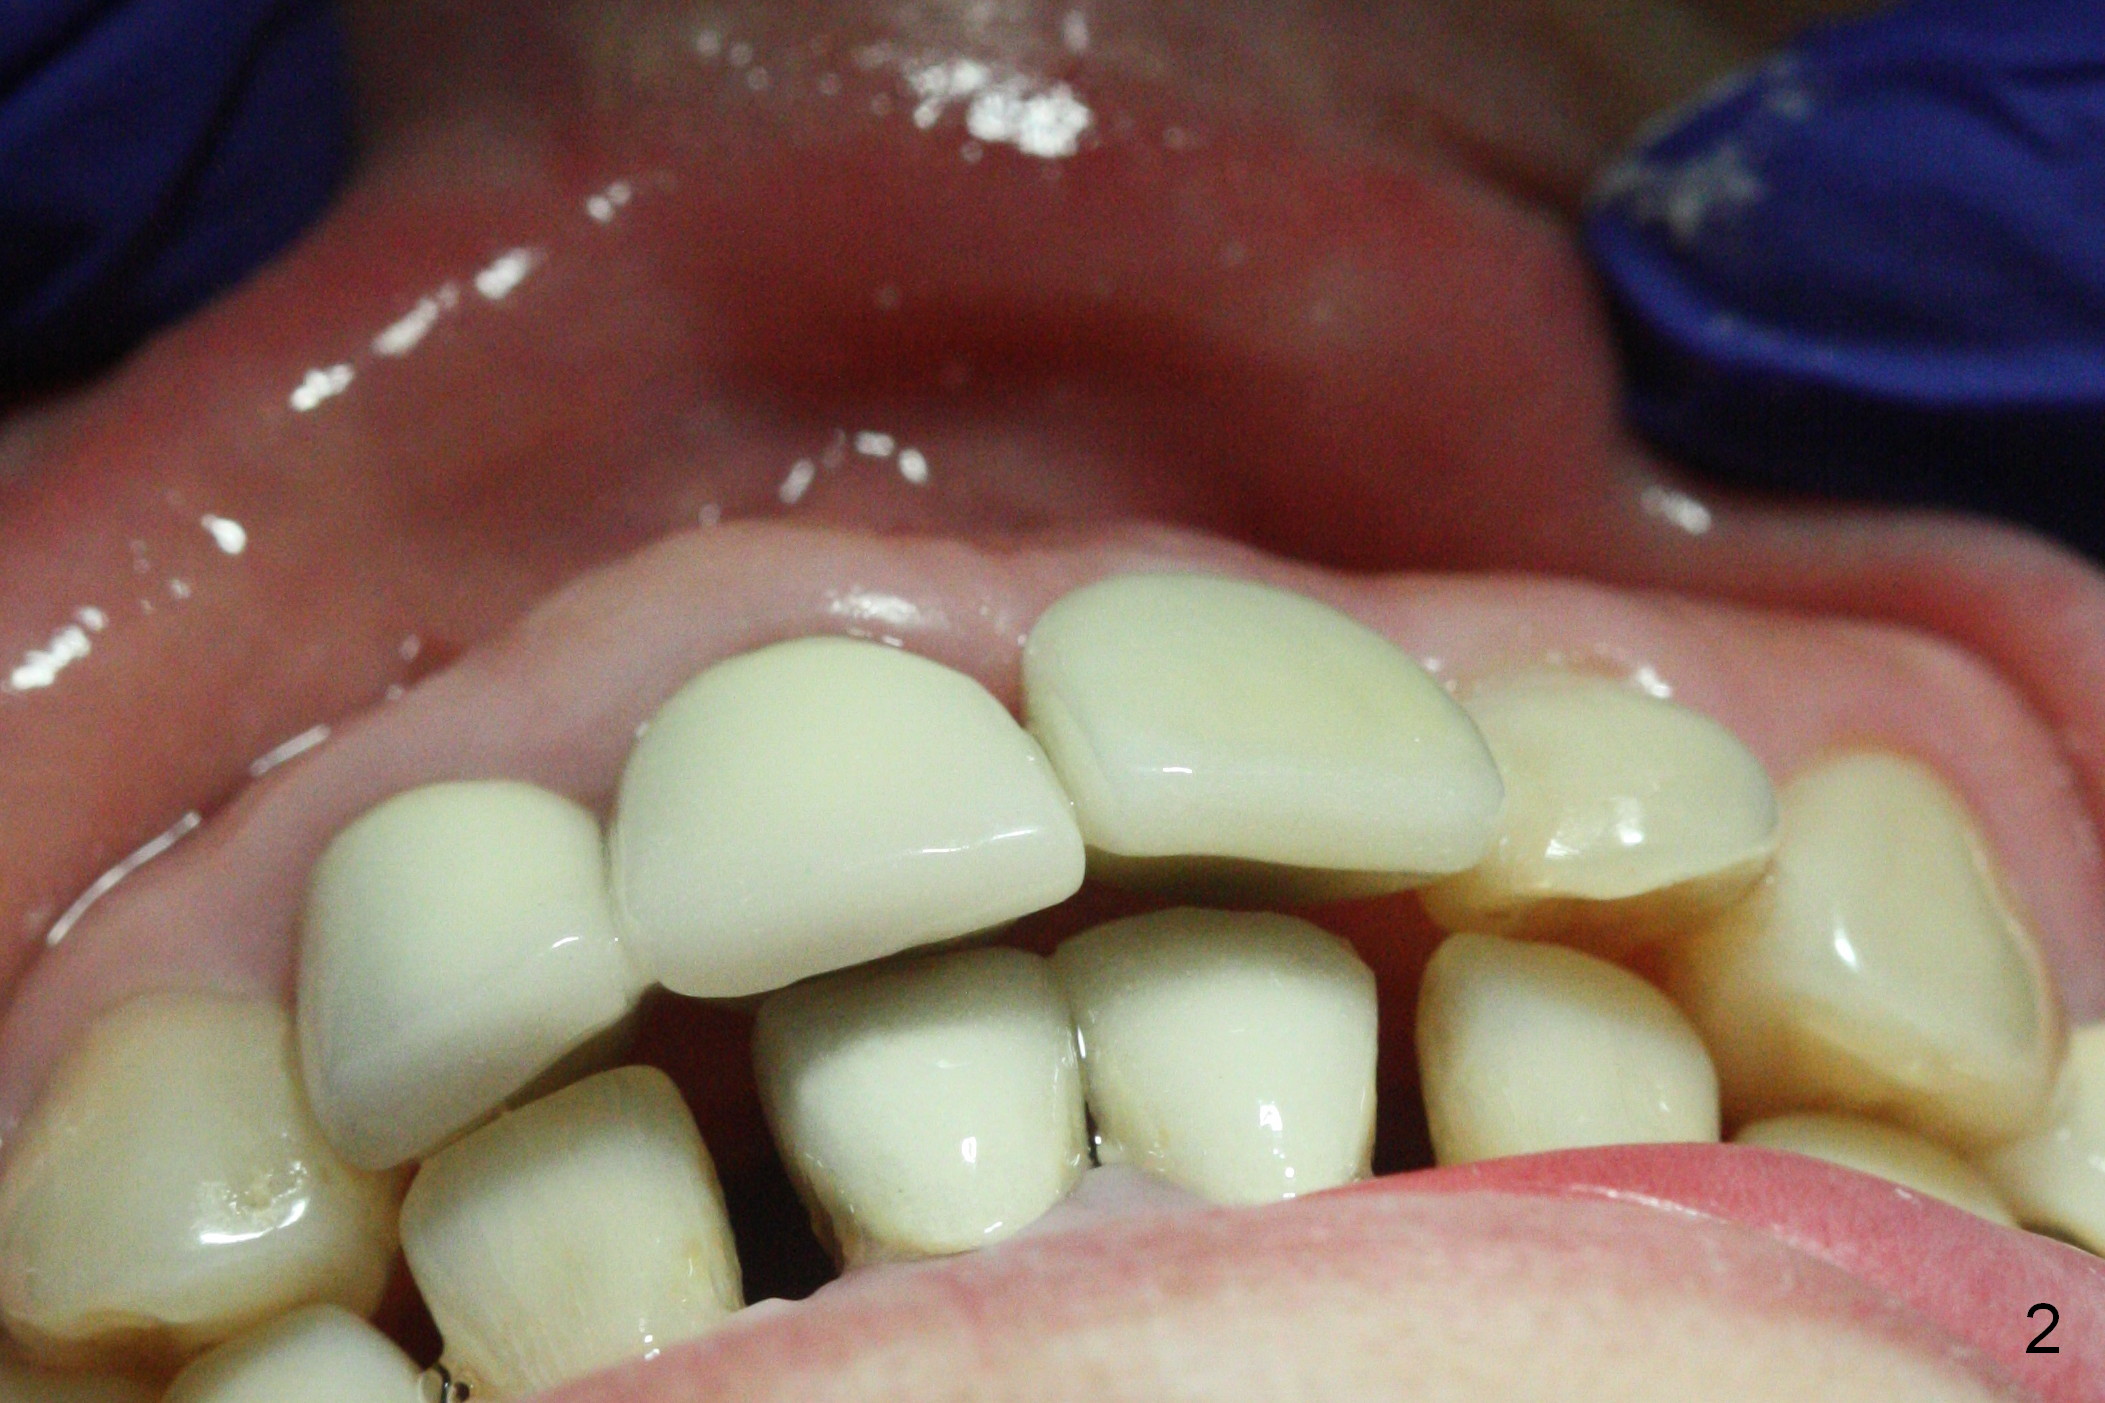

When a permanent crown (Fig.1 C) is seated 5 months postop, it looks too long and bulky (as well as metal show through cervically), which is in turn due to buccal placement of the crown (Fig.2) and abutment (Fig.3).  By mistake, abutment is changed from 4.5x15°, 3 mm cuff to 4.5x15°, 2 mm cuff (Fig.4-6); the profile appears to improve.  After prep (buccoincisal (Fig.4 ^) and linguoincisal), impression is taken.  The gold coating in the buccocervical area is untouched so that there should be no or minimal metal show through.  Please make a new crown as cosmetic as possible (not too bulky, especially buccocervical).  If you feel that the result will be the same as before, return the case.  The angled abutment may be changed 25°.  In fact the new crown looks better.